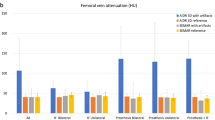

The objective analysis results are displayed in Table 2 and Fig. 2.

a Results of the quantitative image evaluation regarding corrected attenuation. Corrected image attenuation values were closest to 0 in virtual monoenergetic images at 110 keV (VMI110keV) for hyper- and hypodense artifacts in the muscle as well as in artifact-impaired bone and bladder. Corrected image attenuation values close to 0 indicate optimal artifact reduction. b Results of the quantitative image evaluation regarding corrected noise. Corrected image noise showed values closet to 0 in virtual monoenergetic images at 110 keV (VMI110keV) for hyper- and hypodense artifacts in the muscle as well as in artifact-impaired bone and bladder. Corrected image noise values close to 0 indicate optimal artifact reduction